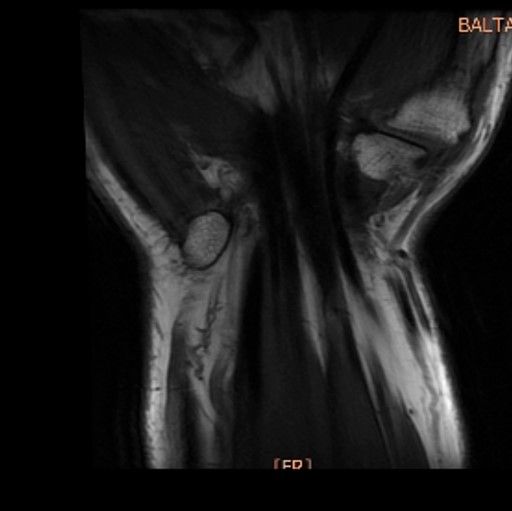

Case 22 - Scaphoid Pseudoarthrosis

57 yr, male, right dominant

Left distal radius fracture 6 years ago

Left wrist ulnar side pain, DRUJ tenderness on dorsal side, ulnar head prominent on volar side, piano key sign: (+)

Palmaris longus (+)